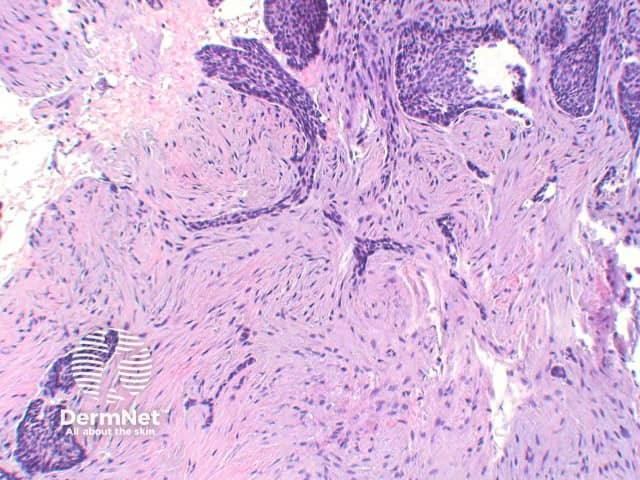

The key feature of basal cell carcinoma at low power magnification is of a basaloid epithelial tumour arising from the epidermis (figure 1). The basaloid epithelium typically forms a palisade with a cleft forming from the adjacent tumour stroma (figure 2). Centrally the nuclei become crowded with scattered mitotic figures and necrotic bodies evident (figure 3). A useful distinguishing feature from other basaloid cutaneous tumours is the presence of a mucinous stroma (figure 4). Some tumours may also show foci of regression, seen as areas of eosinophilic stroma with lack of basaloid nests.

Figure 3